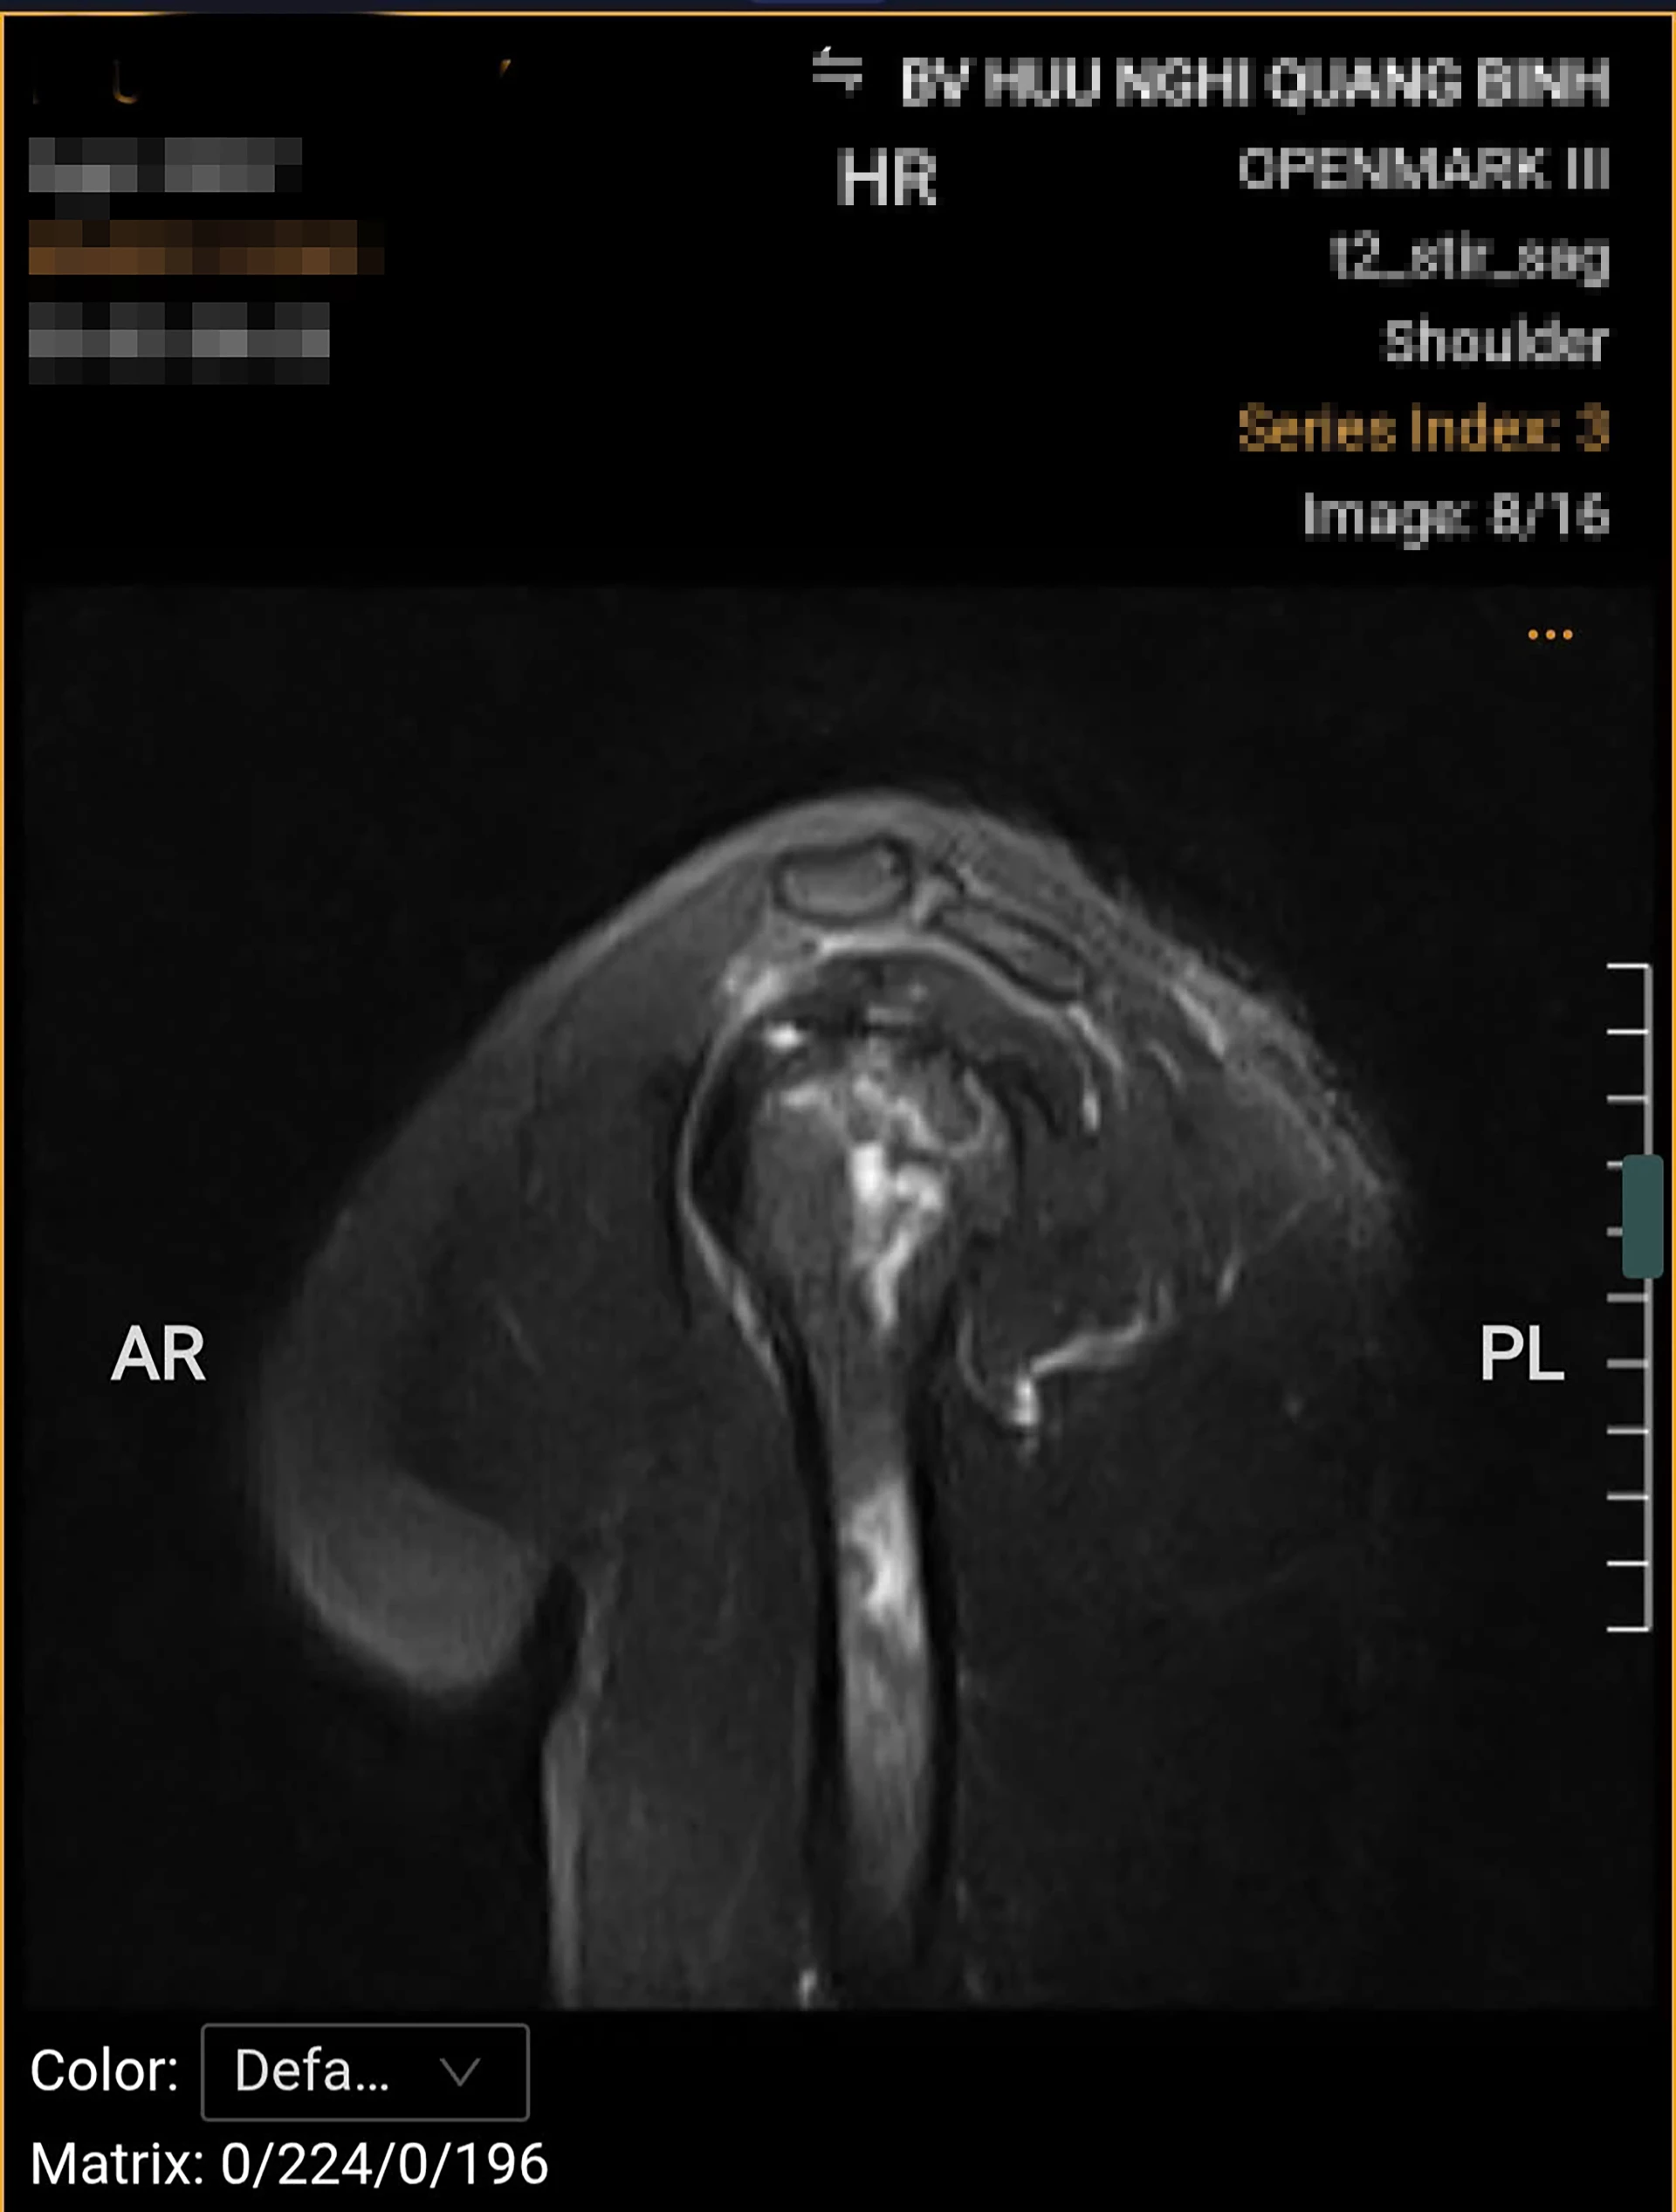

| Bệnh nhân bị hoại tử chỏm xương cánh tay trái. |

Ông N.V.H. (39 tuổi), ở xã Quảng Ninh bị đau nhức vai trái nhiều tuần, cơn đau tăng lên khi nâng tay, dang tay hoặc thực hiện các động tác. Kết quả chụp MRI cho thấy, phần chỏm xương cánh tay trái bị hoại tử, ổ hoại tử lan xuống vùng cổ và thân xương cánh tay. Khi chụp X-quang, phần khớp háng nhận thấy dấu hiệu hoại tử vô mạch chỏm xương đùi hai bên độ 2 theo ficat và alert (tình trạng tế bào xương ở chỏm xương đùi chết đi do mất nguồn cung cấp máu).